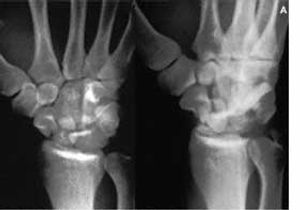

A 22-year-old soldier's left hand, wrist, and distal forearm were crushed by an object that weighed 90.8 kg (200 lb). There were no signs of open fracture; soft-tissue injuries were obvious. No neurovascular deficit was discerned in the limb.